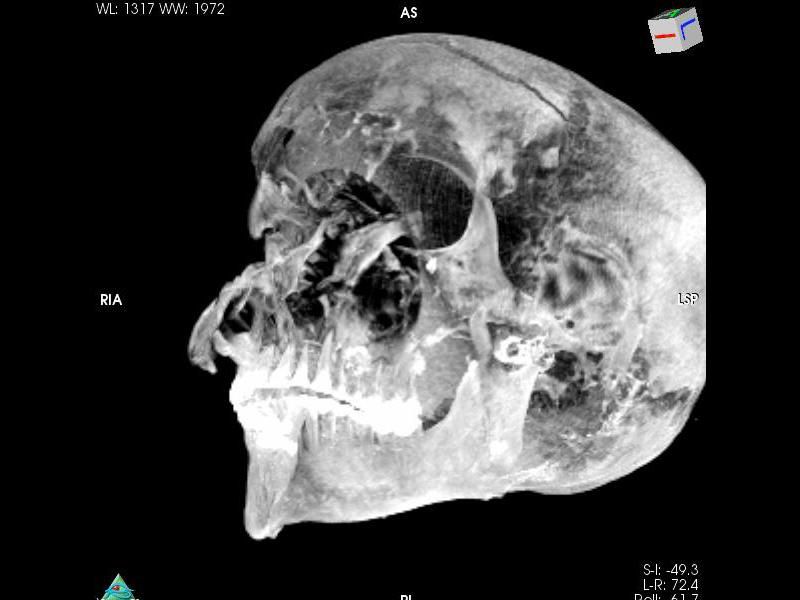

The new study uses X-rays from multiple angles to build a 3D image of the pharaoh’s mummy. The pharaoh’s remains are in poor condition, with bones disarticulated and the head detached from the rest of the body.

Nevertheless, the wounds on the skull tell the story of brutal death. The pharaoh had a 2.75-inch-long (7 centimeters) cut across his forehead, which would have been delivered from an axe or sword stroke from above. This wound alone could have been fatal. Another potentially fatal slice above the pharaoh’s right eye was 1.25 inches (3.2 cm) long and possibly made by an axe. More cuts on the nose, right eye and right cheek came from the right and from above and may have been delivered with an axe handle or blunt staff, the researchers said.

Meanwhile, someone in front of the king swung a sword or an axe at the pharaoh’s left cheek, leaving another deep slice. From the left, a weapon — probably a spear — penetrated the base of his skull, leaving a 1.4-inch-long (3.5 cm) wound.

Early archaeologists had previously reported many of these wounds, but Saleem and her colleague, Egyptologist Zahi Hawass, discovered a new set of skull fractures covered by embalming material. Concentrated on the right side of the skull, the damage seems to have been caused by a dagger and a heavy, blunt object, perhaps an axe handle.